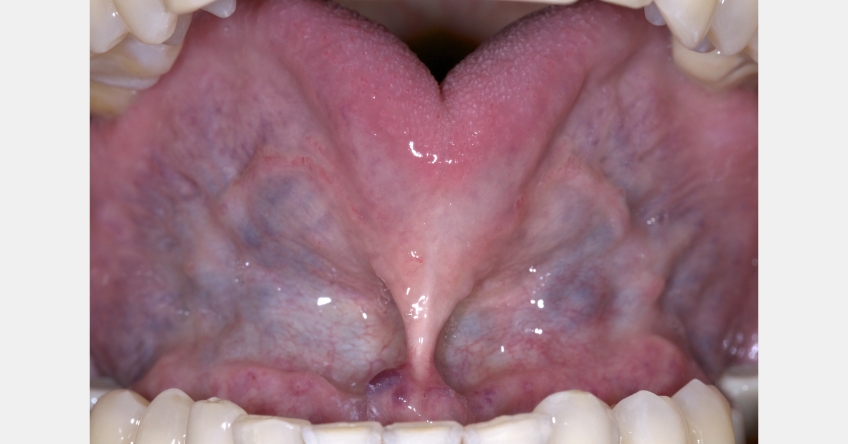

Tongue ties limit tongue movement. The inability to move the tongue correctly impairs oral function: sucking, chewing, swallowing, and speaking. It can also compromise the ability to breastfeed, a principal factor in craniofacial development. In addition, the inability to maintain force in the palate while breathing through the nose appears to alter the growth of the maxilla.

The tongue tie is a direct and indirect factor in apnea. The restriction prevents the tongue from rising out of the throat and sitting against the palate, which can be a direct cause of apnea. Indirectly, the inability to position the tongue on the palate alters the growth and development of the oral and nasal cavities.